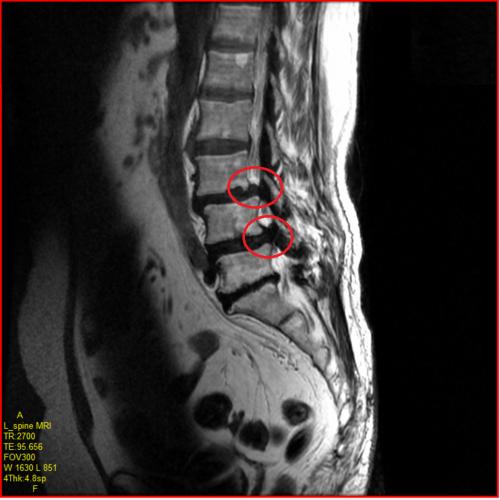

허리협착증(요추관협착증)은 척추 중앙의 통로인 척추관이 좁아져 신경을 압박하는 질환입니다. 30세 이후부터 디스크와 척추 인대가 퇴행성 변화를 시작하면서, 50대 이상에서 특히 흔하게 발생합니다. 60대 이상의 약 50%가 이 질환을 가지고 있을 정도로 매우 흔합니다.

가장 특징적인 증상은 앞으로 숙이거나 앉을 때는 편하지만, 서 있거나 뒤로 젖힐 때 심해진다는 것입니다. 이 특징이 운동 선택에 매우 중요합니다.